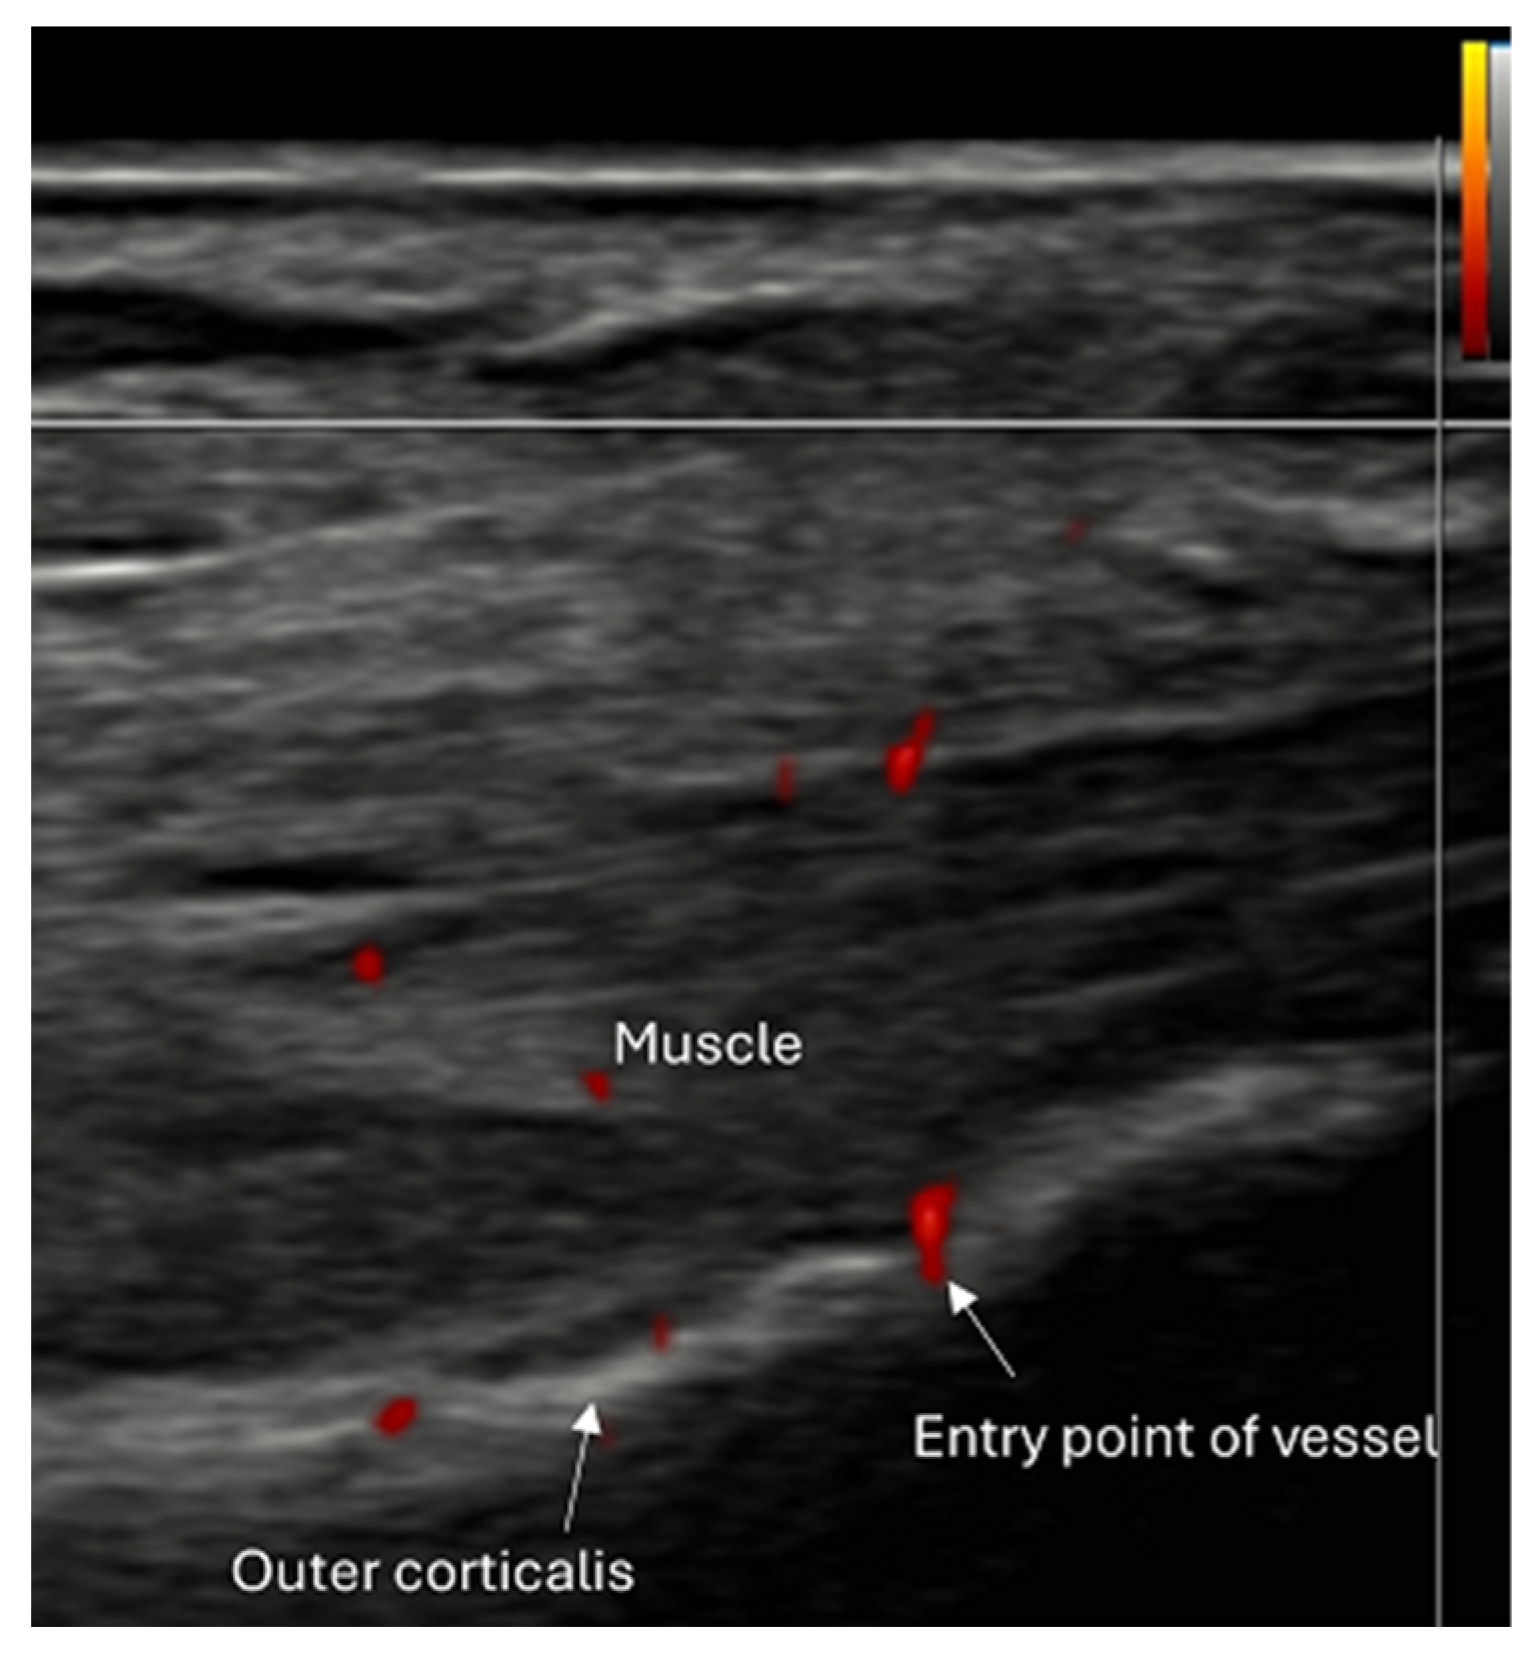

- Use of color and power Doppler: When employing Doppler techniques to assess vascularity related to inflammation or healing, care must be taken to avoid excessive probe pressure. Over compression of the tissue can collapse small vessels, leading to false-negative findings.

- Fracture healing monitoring: Ultrasound facilitates early callus formation. This can be useful for radiation-free monitoring of healing progression.